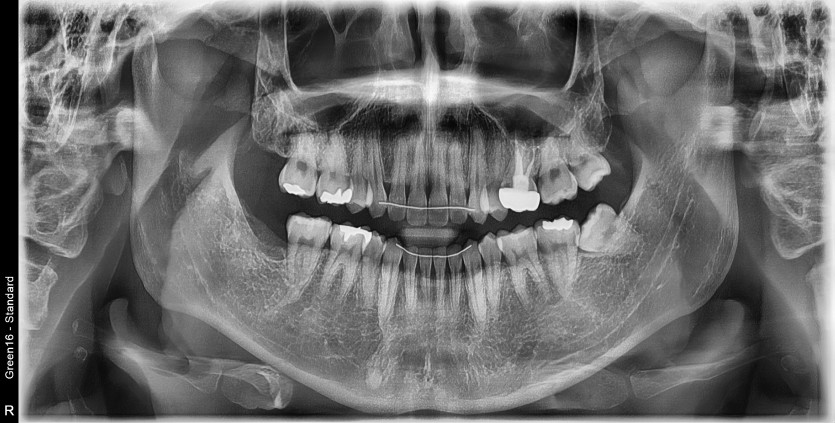

#28,38 사랑니 발치

구강 외과 전문의가 당일 발치했습니다.